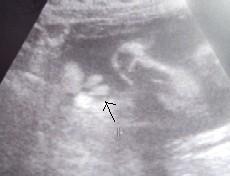

In der 19. Woche tendierte mein FA zum Mädchen, wollte sich aber noch nicht festlegen - und in der 29. Woche gab er 100 %. Wir bekamen ein Ultraschallbild mit dem "Beweis" und er sagte, wenn sie uns im KH einen Jungen überreichen wollen, sollen wir das Foto zeigen und sagen, dass das nicht angehen kann...

Hier kommt mal das Beweisfoto...